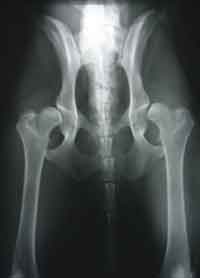

HD (Hüftgelenksdysplasie)

HD ist eine Fehlbildung der Hüftgelenke - das heißt Oberschenkelkopf und Gelenkpfanne passen nicht korrekt aufeinander. Diese Fehlbildung kann unterschiedlich ausgeprägt sein und tritt oft beidseitig auf.

Norberg Winkel

HD-Grade

Wir unterscheiden zwischen 5 verschiedenen Schweregraden der HD.

HD-frei - A

Das Gelenk ist absolut unauffällig und der Norbergwinkel beträgt 105 Grad oder mehr

HD-Verdacht/Grenzfall - B

Der Norbergwinkel beträgt 105 Grad oder mehr und die Gelenkpfanne und/oder der Schenkelkopf sind leicht ungleichmäßig oder aber Gelenkpfanne und/oder Schenkelkopf sind gleichmäßig, aber der Norbergwinkel beträgt weniger als 105 Grad

leichte HD -C

Norbergwinkel 100 Grad oder kleiner, ungleichmäßiger Oberschenkelkopf und Gelenkpfanne. Unter Umständen sind auch schon leichter arthrotischer Veränderungen zu bemerken.

mittlere HD - D

Norbergwinkel größer als 90 Grad und deutliche Ungleichmäßigkeiten von Oberschenkelkopf und Gelenkpfanne. Veränderungen des Pfannenrandes und/oder arthrotische Veränderungen sind zu erwarten oder schon vorhanden.

schwere HD - E

Norbergwinkel weniger ald 90 Grad, abgeflachter Pfannenrand, auffällige Veränderungen an Oberschenkelkopf und Gelenkpfanne. Deutliche arthrotische Veränderungen sind zu erwarten oder schon vorhanden.